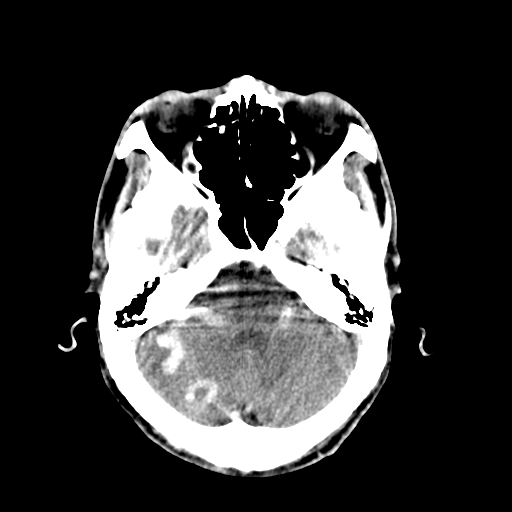

标题: CT17002:M48Y,血管畸形,血管瘤,请鉴赏! [打印本页]

标题: CT17002:M48Y,血管畸形,血管瘤,请鉴赏!

男48y,头痛多年,加重一天!

典型的血管畸形---avm  -----右侧枕顶叶及侧脑室三角区等高混杂密度影夹杂少许低密影显示,无明显水肿,增强可见明显的供血动脉与引流静脉显示